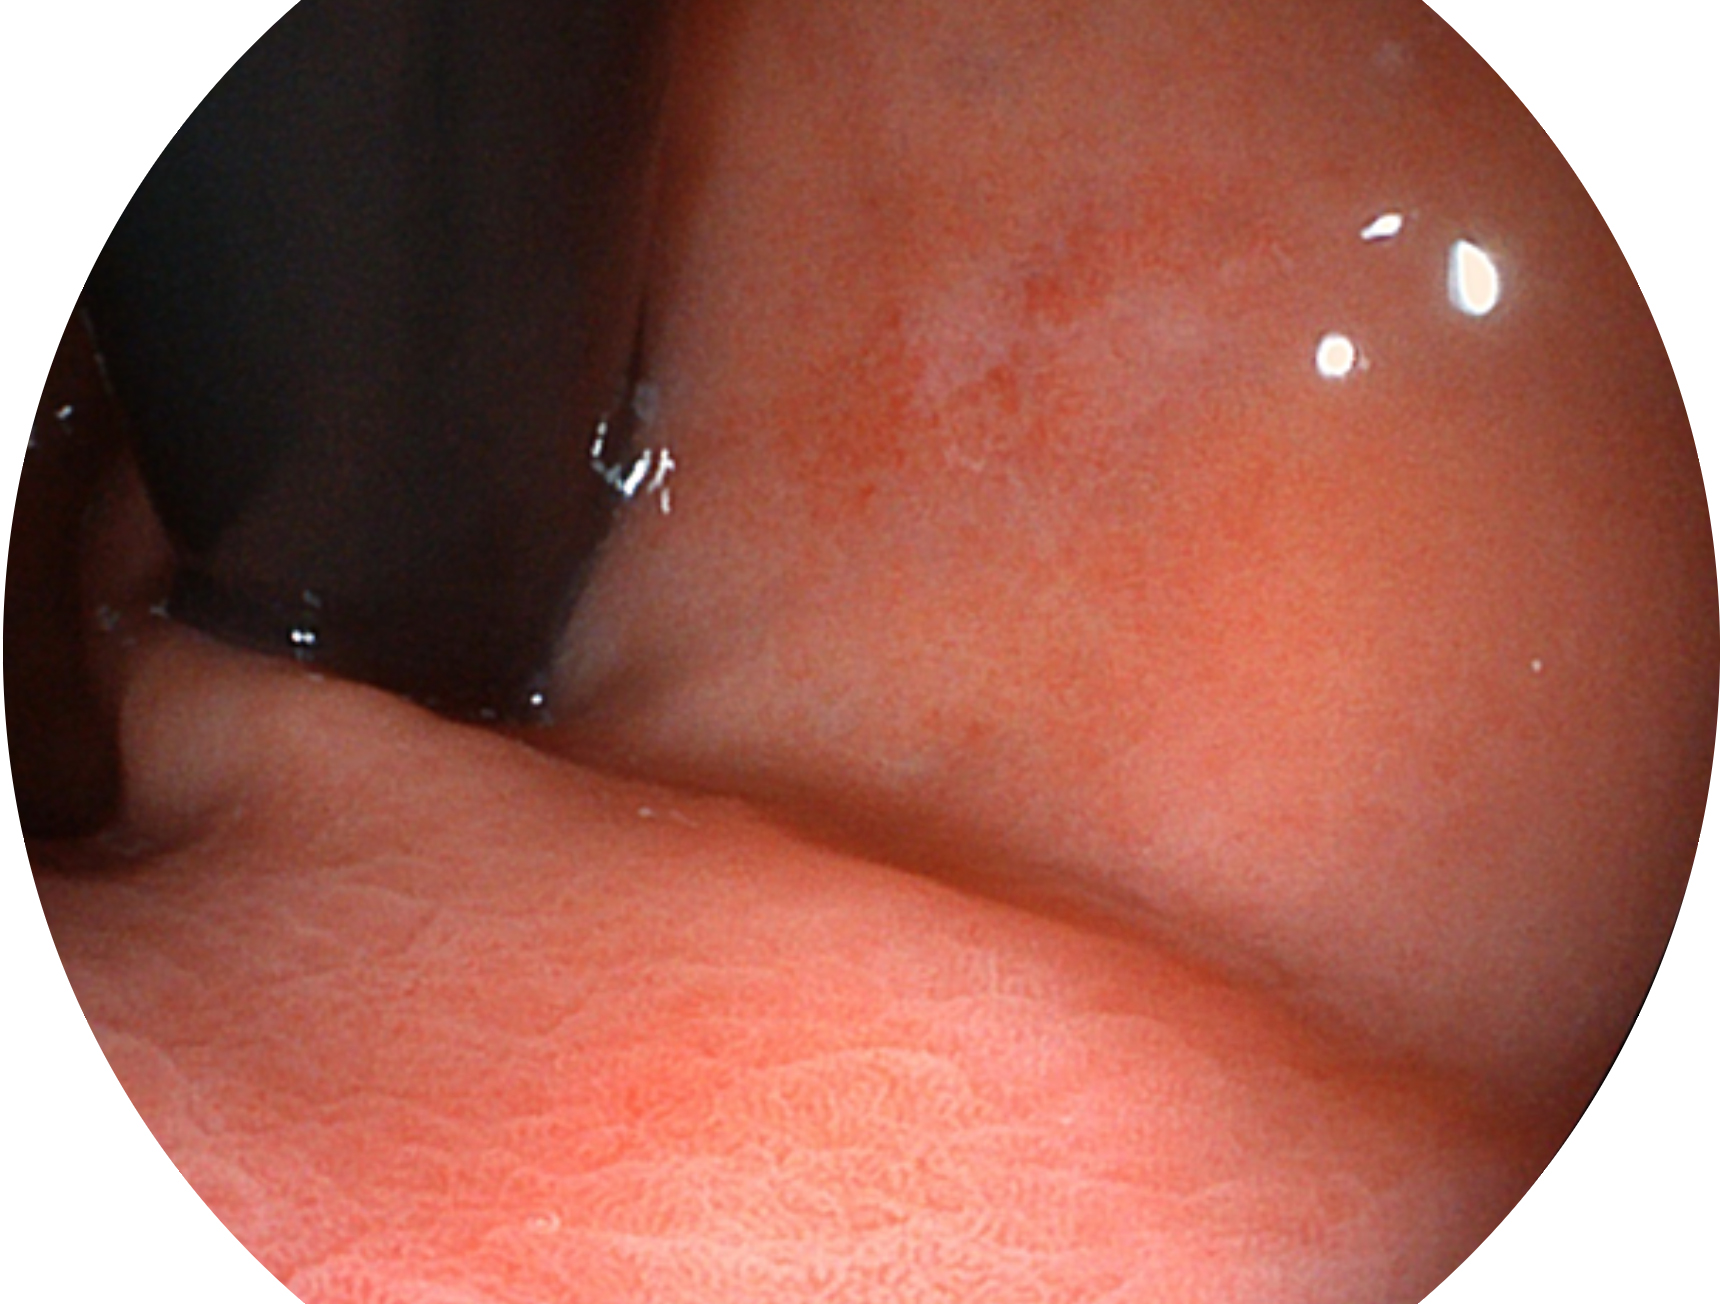

• 白光图像 SFI图像